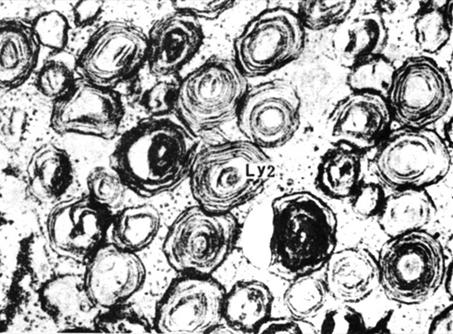

台-萨氏综合征(Tay-Sachs diesease):要叫黑蒙性家族痴呆症,溶酶体缺少氨基已糖酯酶A(β-N-hexosaminidase),导致神经节甘脂GM2积累(图6-30),影响细胞功能,造成精神痴呆,2~6岁死亡。患者表现为渐进性失明、病呆和瘫痪,该病主要出现在犹太人群中。

图6-30 台-萨氏综合征神经元中同心圆状的溶酶体 引自《细胞生物学超微结构图谱》1989